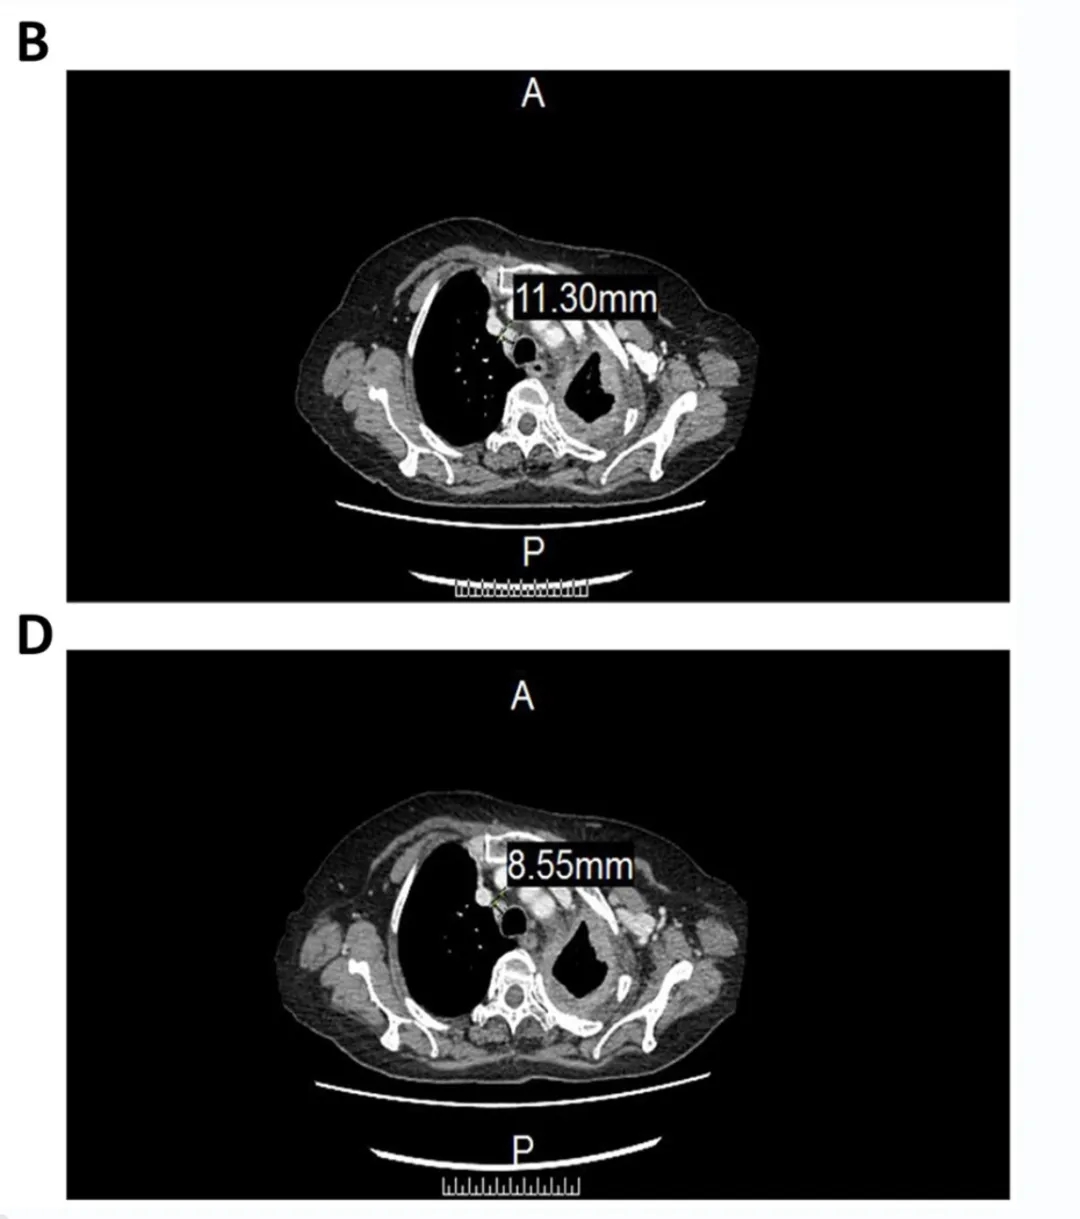

该患者经过3个周期的治疗后,CT图像显示,CCCR-NK92细胞疗法对肿瘤的治疗具有一定的疗效,具体如下。

1、该患者气管前-后腔静脉间质区的淋巴结,从11.3mm(毫米),减少至8.55mm(详见图B、D)。

▲图源“Sage Journals”,版权归原作者所有,如无意中侵犯了知识产权,请联系我们删除

2、左肺包裹的胸腔积液,从46.22mm(毫米)减少至33.59mm(图A、C)。